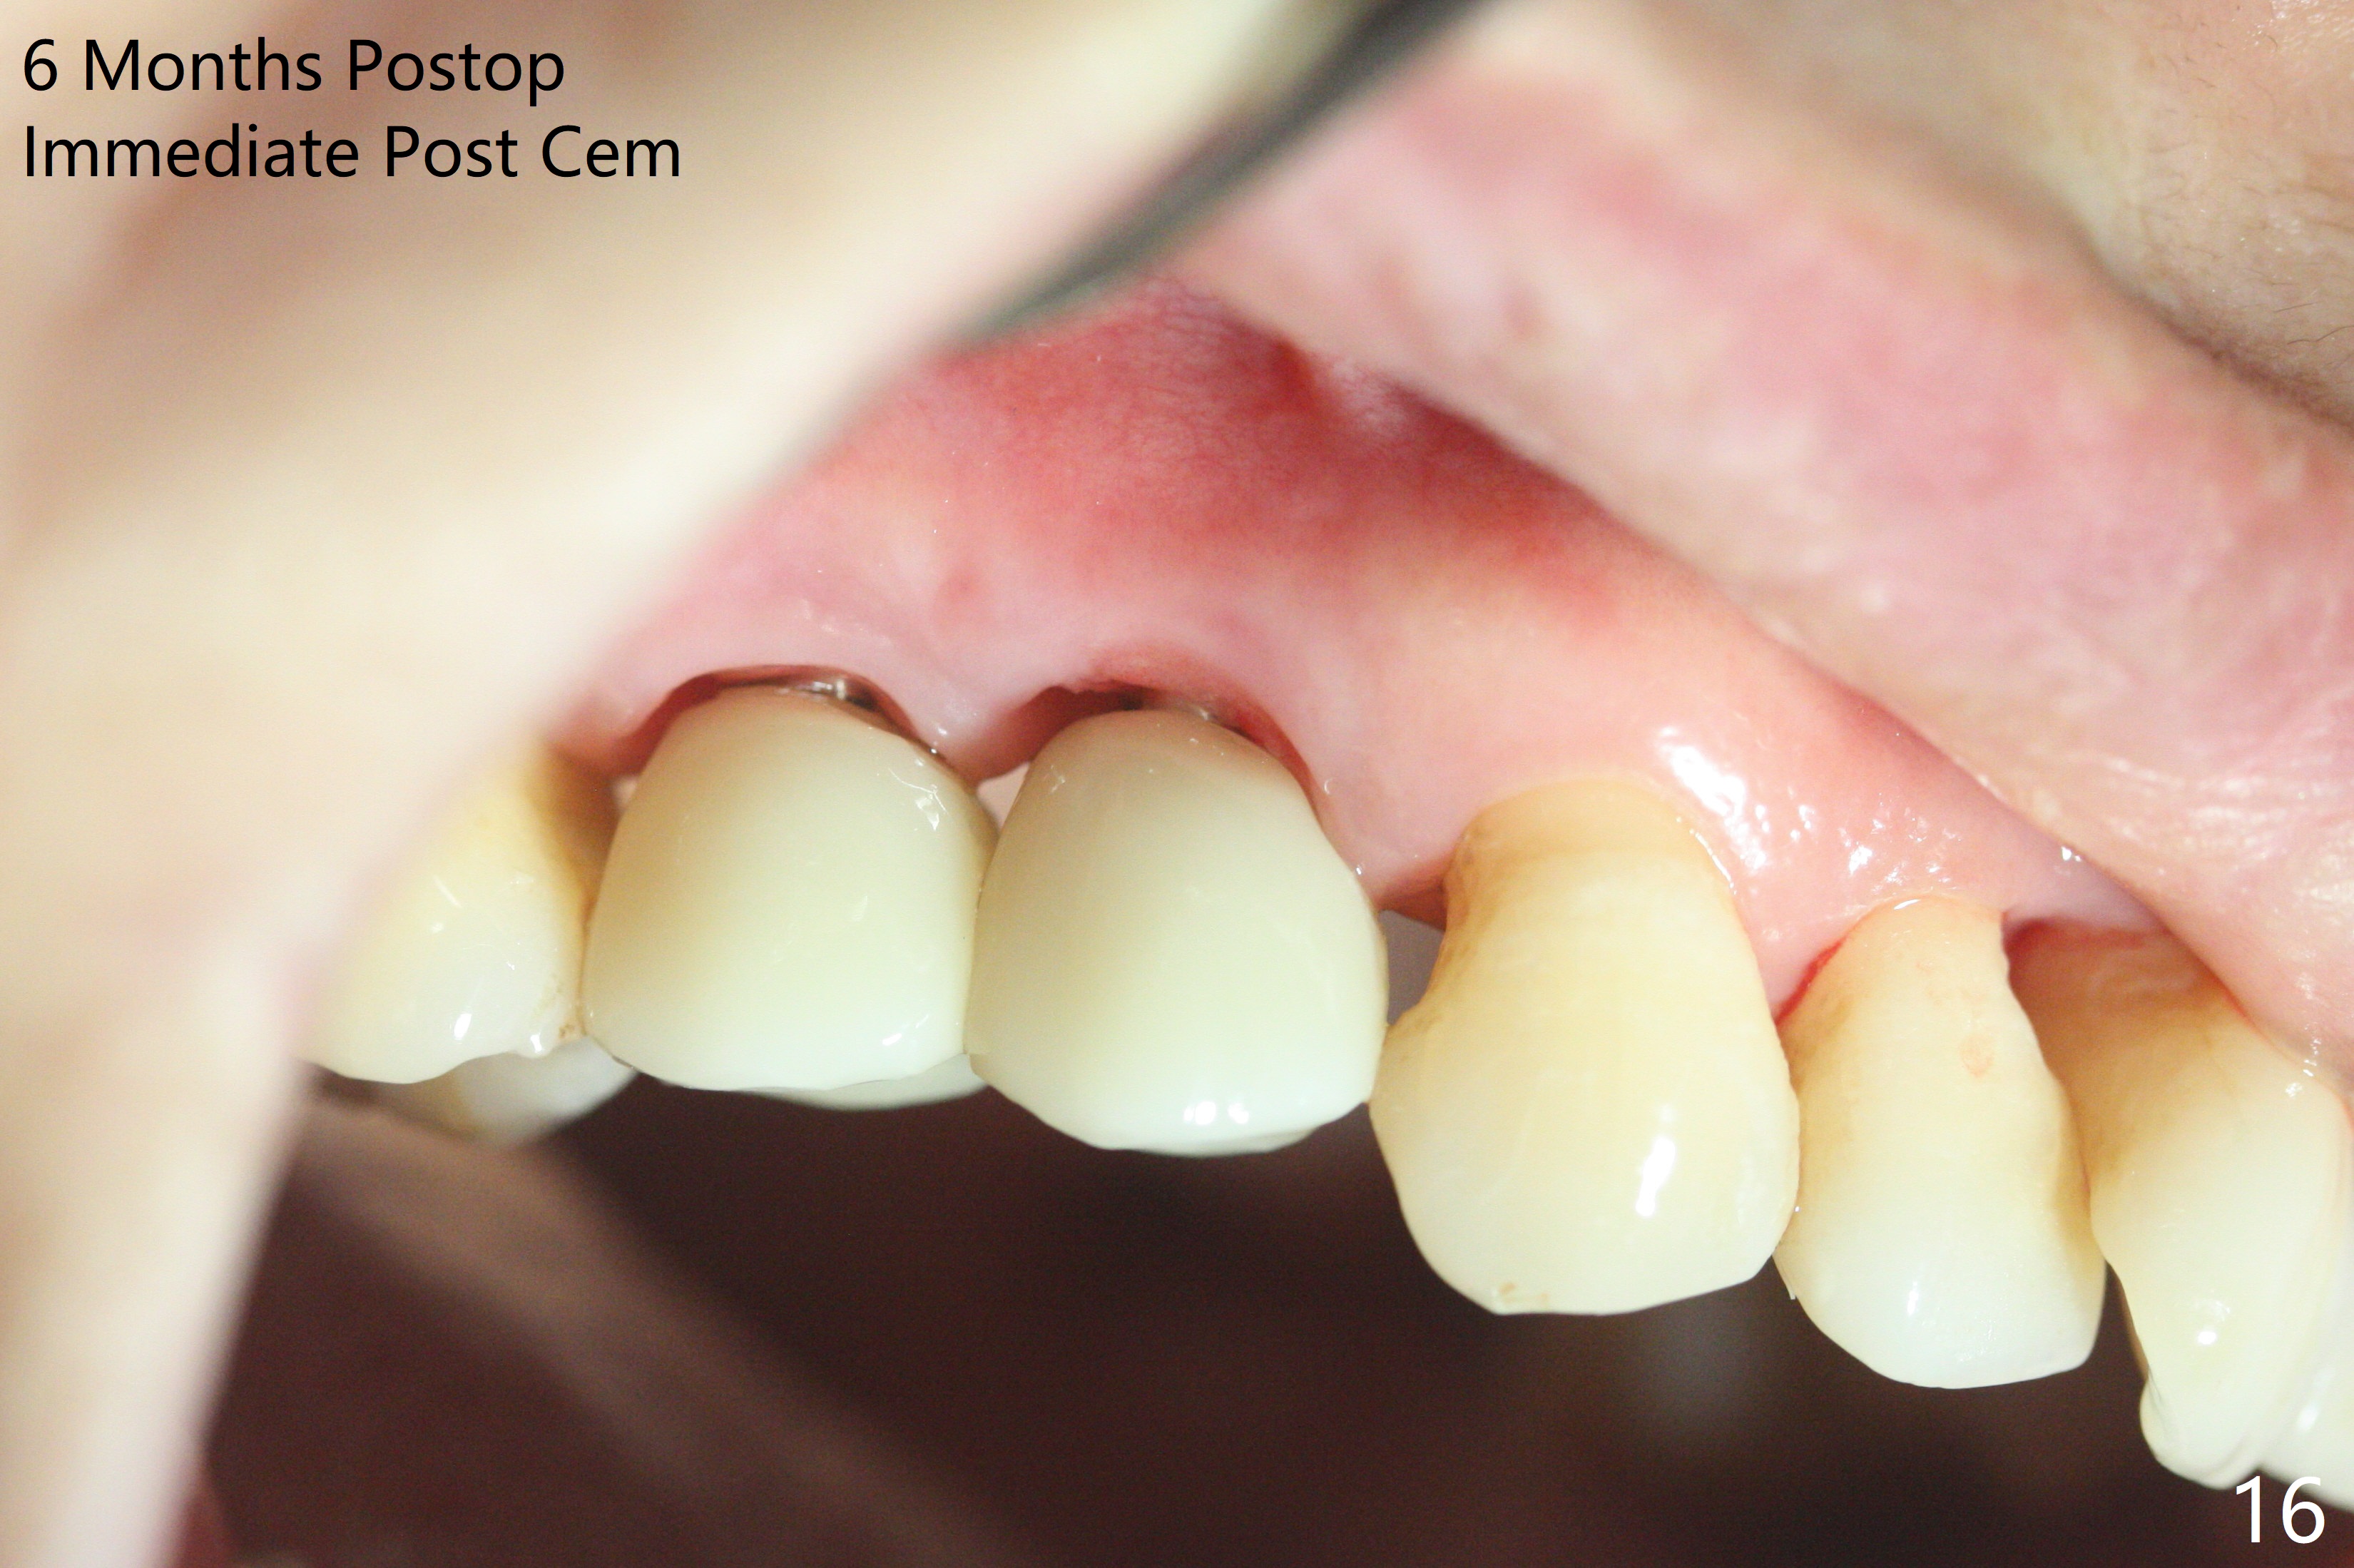

术前CT显示右上4牙槽骨比5窄(图一,二),3.5毫米植体比较合适,况且牙龈厚,基台长的一段式植体显得得当。为了取得最好的植体方位,4先拔除(图三),种植(图四),调整后者深度后,拔除5(术前征求病人同意),开始钻洞(图五),完成种植(图六)。粘性骨粉不仅放置于植体周围,而且6牙根近中(图七),4/5牙槽嵴和龈乳头(P)之间,减少术后龈乳头萎缩(图八:*)。制作两个分开临时牙冠,有利于维持龈乳头。对于病人来说,临时牙冠帮助咀嚼,而对侧拔牙创无法吃饭。术后3个月两个分开临时牙冠(其中一个龈方移位(图九:箭头)保持龈乳头(*)和牙龈外形(图十:*)。临时牙冠取出后,调整基台高度,少量钛屑(不妨大局)附着在健康的牙龈沟(图十一),再次显示两个基台之间龈乳头(图十二:*),衬里,修整的临时牙冠又插回牙龈沟(图十三:箭头),继续维持软组织形态,准备一个月后,调整基台边缘(图十二:箭头),取模。术后五个月大部分骨粉依然保留在植体和邻牙周围,龈乳头退缩不多(图十四: P)。三个月后(术后六个月)钛削无影无踪(图十五,与图十一对比))。永久性牙冠周围空间慢慢会消失(图十六,使用临时性胶水)。